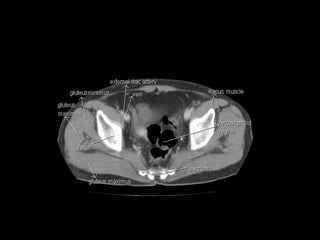

Radiographers use medical imaging equipment like X-rays and MRIs to produce images of patients' internal structures and organs. They are responsible for positioning patients, operating scanning machines, and ensuring quality images. Radiographers must have strong attention to detail, excellent communication skills, and the ability to work well under pressure to accurately capture anatomical features and diagnose any abnormalities.